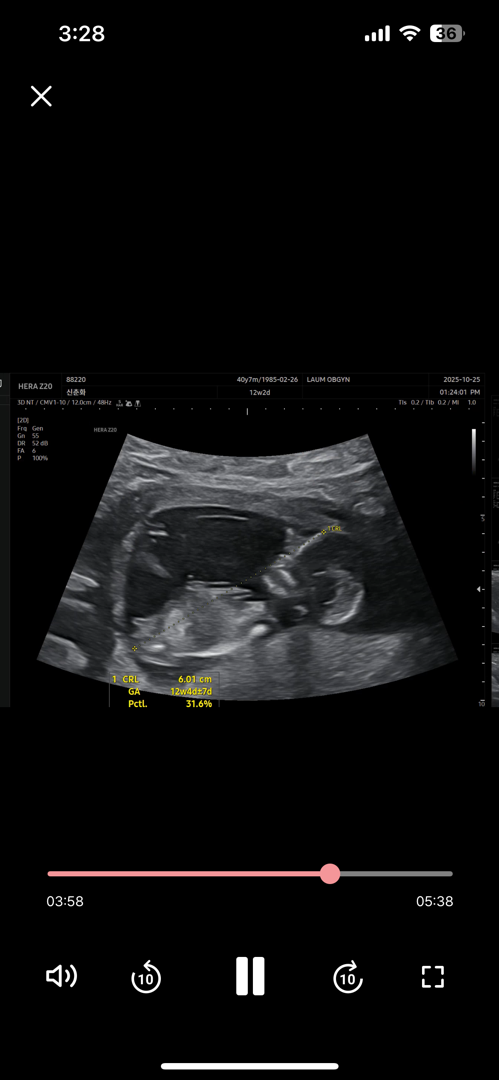

12주2일 각도법 봐줘요

제눈엔 딸로 보이는뎅 맘들은요?